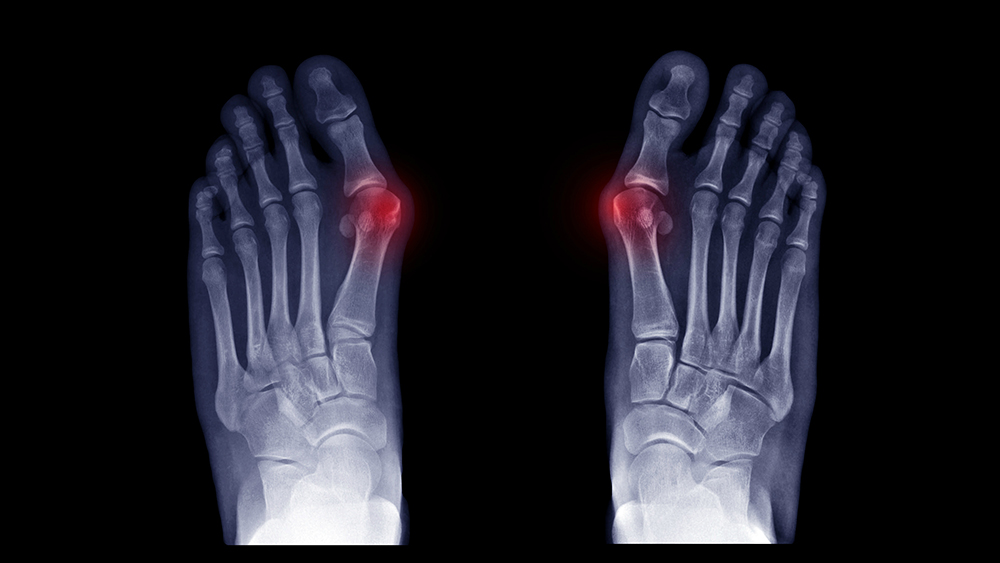

OPERACJA/PLASTYKA PALUCHA KOŚLAWEGO, SZPONIASTEGO, MŁOTOWATEGO.

Operacja plastyczna najczęstszej deformacji nabytej czyli palucha koślawego jest zabiegiem operacyjnym mającym na celu uwolnienie pacjenta od dolegliwości bólowych po przyśrodkowej stronie palucha (tzw: bunionu) oraz na podeszwie stopy wynikające z płaskostopia poprzecznego wystepujące zwykle wtórnie do palucha koślawego przy współistniejącej poprawie efektu wizualnego samej stopy. Bardzo częstą deformacją współistniejącą do palucha koślawego są palce młotowate lub/i szponiaste, które także poddaje korekcji się podczas tego samego zabiegu operacyjnego dla uzyskania pełnego efektu terapeutycznego.

Wskazania do zabiegu to m.in. :

Paluch koślawy

Nawrót deformacji palucha po leczeniu operacyjnym

Deformacje pozostałych palców stopy

Palec V stopy zachodzący.

Przed przystąpieniem do zabiegu konieczna jest konsultacja z jednym z naszych lekarzy, który zbierze ogólny wywiad, oceni stan ogólny kliniczny pacjenta, wykona USG oraz zleci odpowiednie niezbędne badania - zwykle jest to RTG stóp w kilku projekcjach w pozycji stojącej - pozwalające zaplanować szczegółowo zakres operacji.

Przebieg pozabiegowy: Jeszcze tego samego dnia pacjent jest usprawniony przy asyście fizjoterapeuty - nauka chodzenia o kulach łokciowych z pełnym obciążaniem kończyny operowanej zabezpieczonej w specjalnej ortezie mające na celu jak najszybsze odzyskanie samodzielności. Czas w jakim pacjent wraca do aktywności sportowej wynosi około 3 miesiące. Czas spędzony w szpitalu wynosi 1-2 dni, w zależności od rozległości procedury.